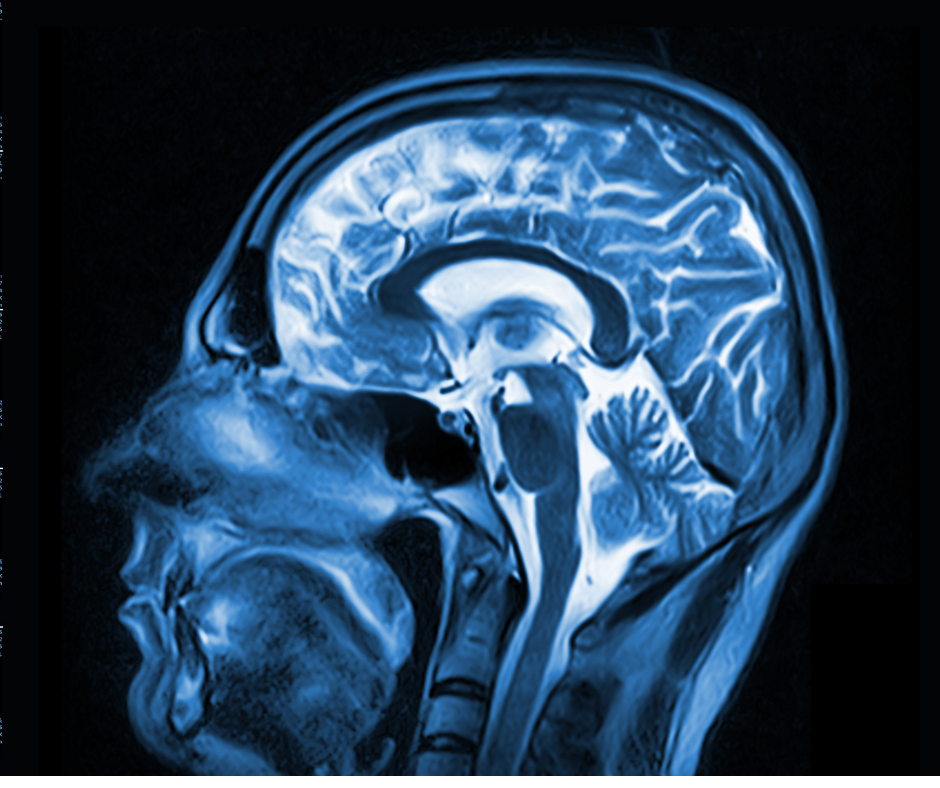

In comparison to neuroradiology assessment of brain magnetic resonance imaging (MRI) scans for tumor diagnosis, researchers found that adjunctive use of a deep learning system improved diagnostic accuracy by 12.4 percent and sensitivity by 33.5 percent in one test set of 300 patients.

The Maestro Brain Model reportedly provides automated identification, quantification and labeling of brain structures on magnetic resonance imaging (MRI).